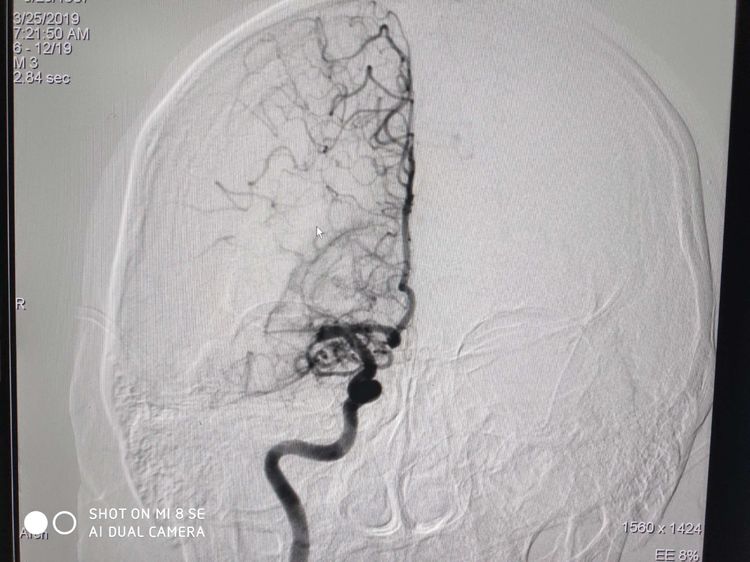

术后:造影后血管再通良好,转入神经内科抢救室继续围手术期治疗。目前患者偏瘫侧肢体肌力逐渐恢复接近正常。期待患者早日康复。???